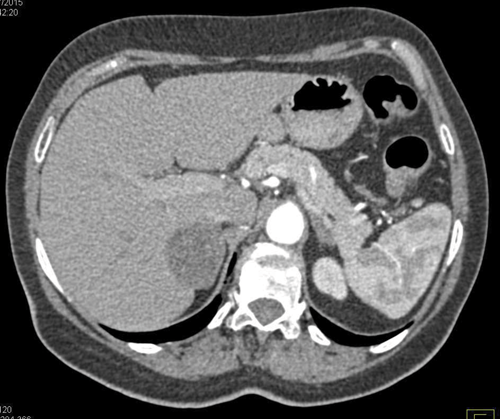

A 45-year-old man undergoes a CT of his abdomen to stage a newly diagnosed bowel malignancy.

An enlarged right adrenal gland, with a smooth contour and homogenous appearance.

Smooth, homogenous solitary lesion <4cm with <10HU (i.e. lipid rich), with >60% contrast washout.

An MRI scan is as effective as CT for detecting benign from malignant lesions. Non-functional adenoma on T2 imaging have the same density as the liver, with rapid washout of contrast. Malignant lesions show intermediate to high density on T2 imaging, with rapid and intense enhancement.

Risk of malignancy is 1%, but given the fact that he has a history of bowel cancer this increases to 75%. Therefore 25% risk it is benign.